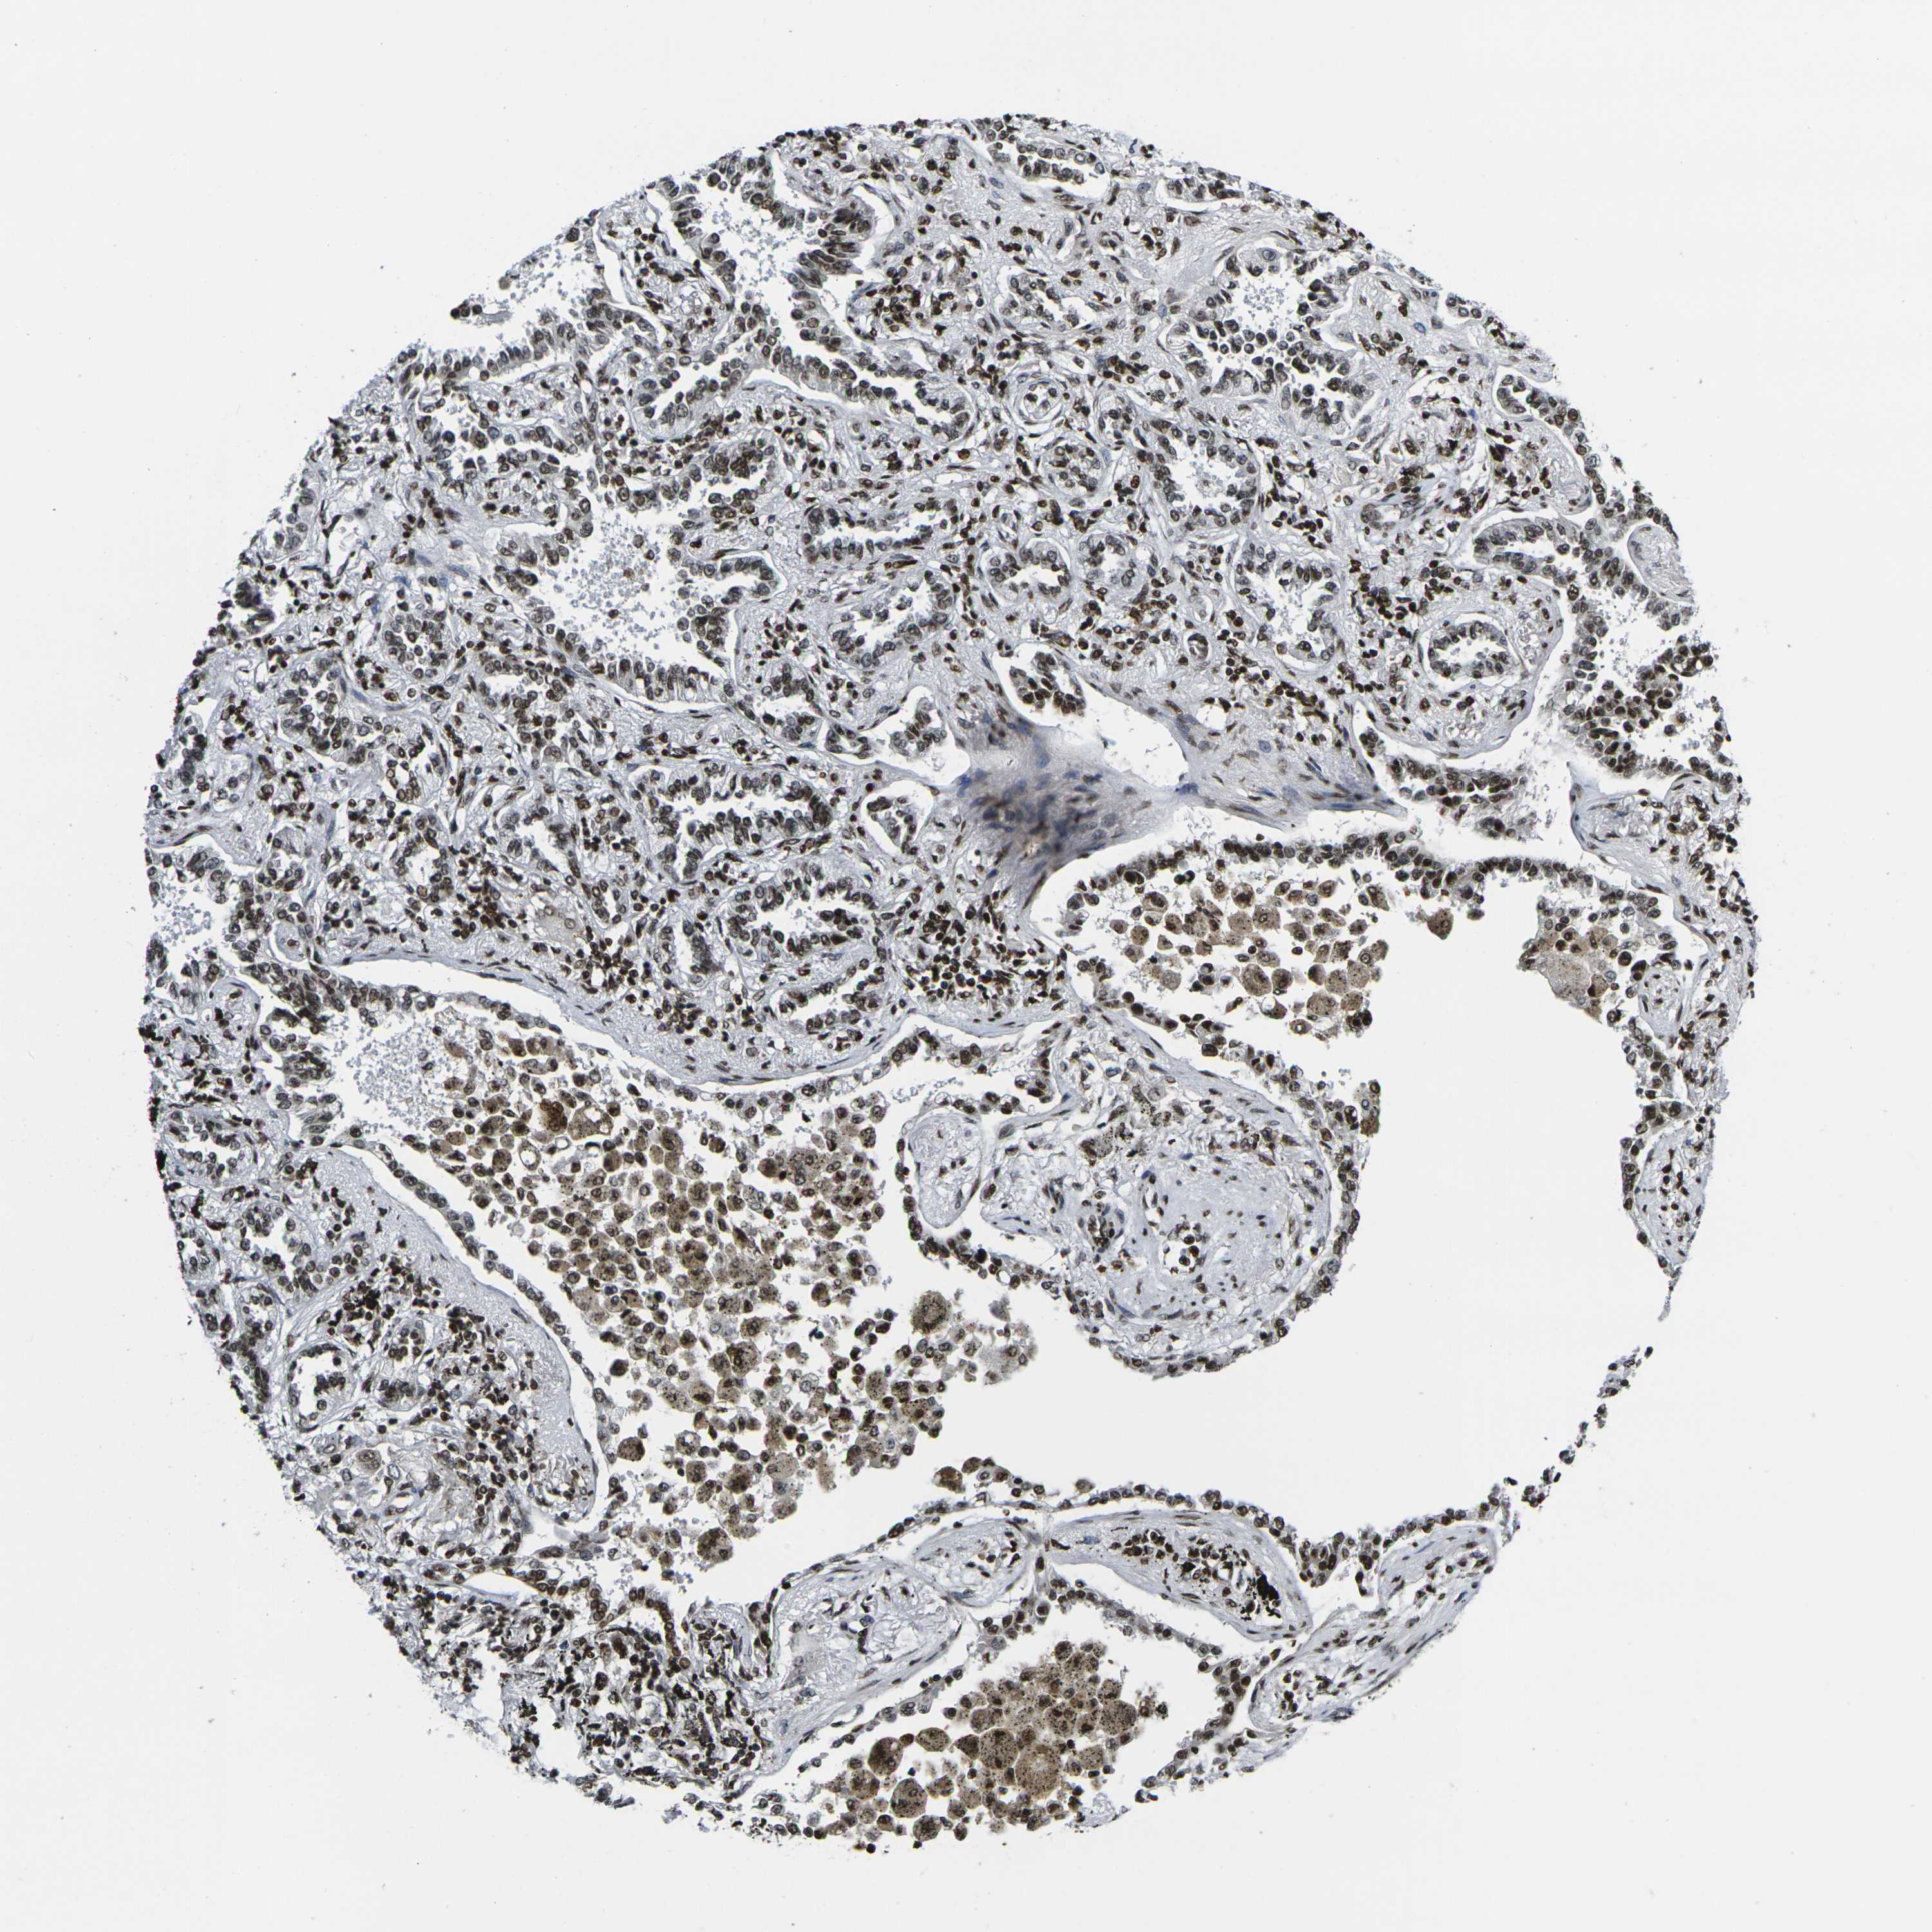

CANCER LUNG CANCER Show tissue menu

H1-10 is not prognostic in Lung Squamous Cell Carcinoma (TCGA)

Stage: